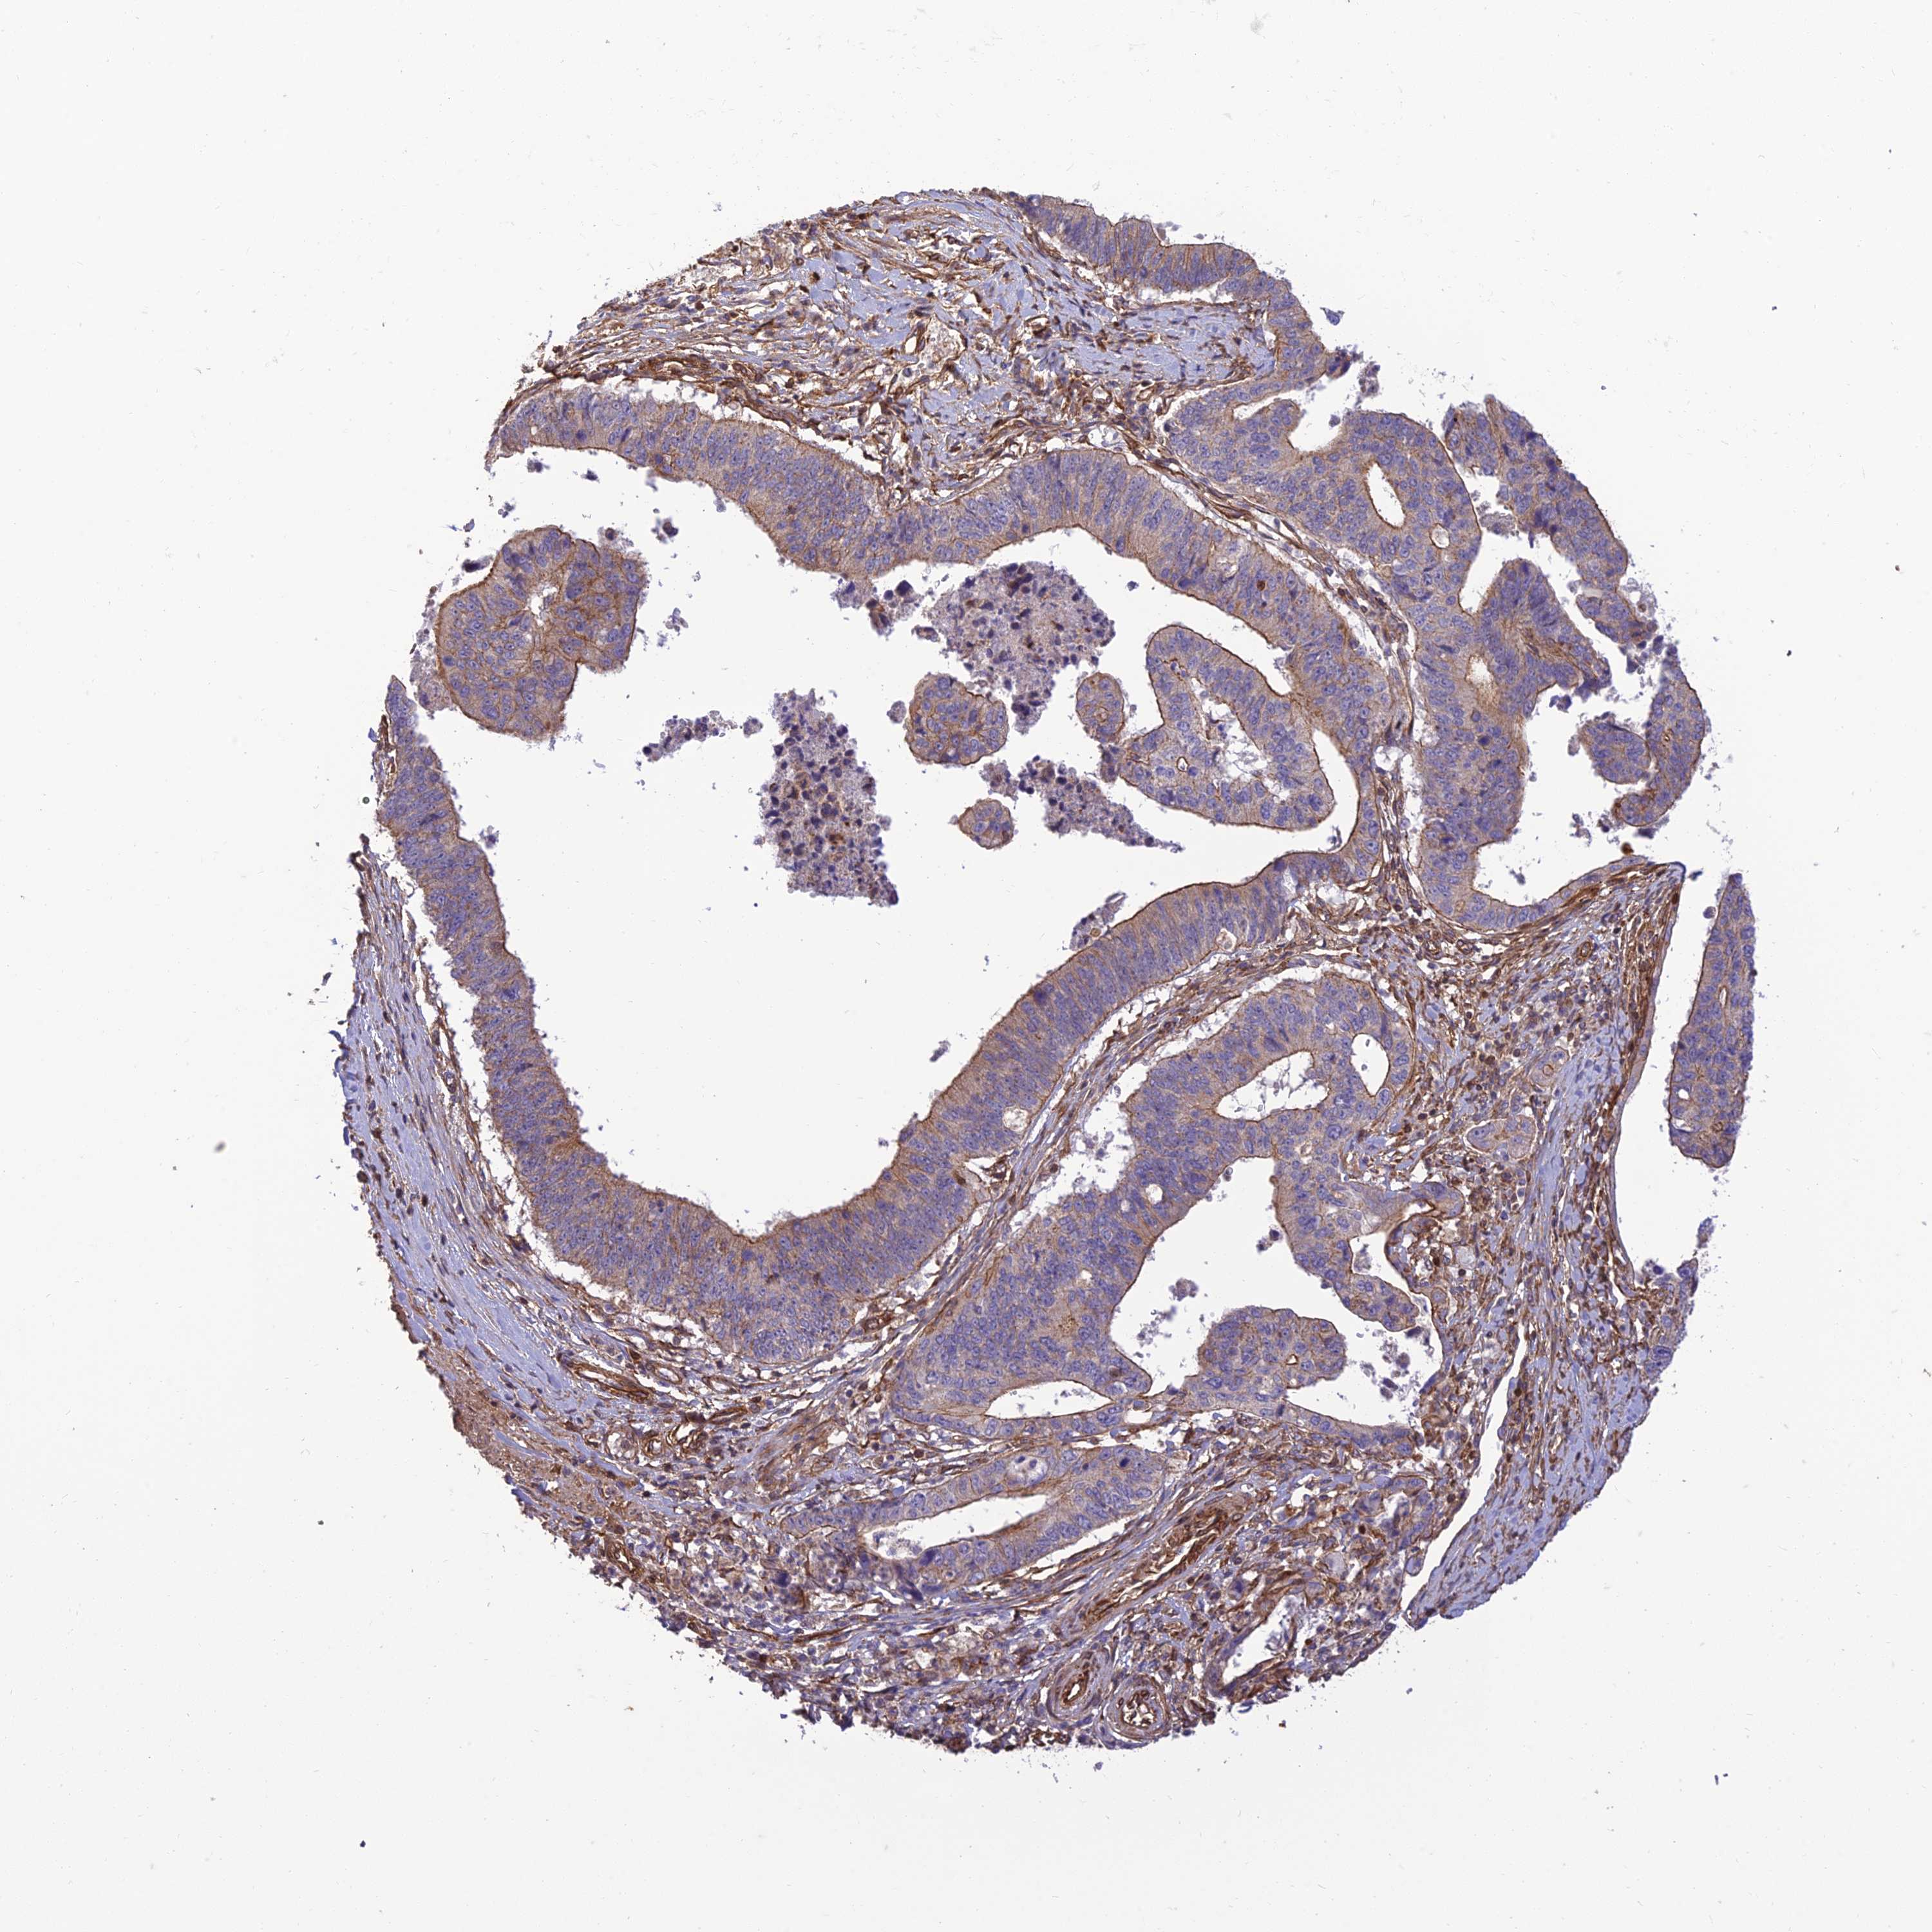

STOMACH CANCER - Protein expressioni

A mouse-over function shows sample information and annotation data. Click on an image to view it in a full screen mode. Samples can be filtered based on level of antibody staining by selecting one or several of the following categories: high, medium, low and not detected. The assay and annotation is described here.

Note that samples used for immunohistochemistry by the Human Protein Atlas do not correspond to samples in the TCGA dataset.

Antibody stainingi

Antibody staining in the annotated cell types in the current human tissue is reported as not detected, low, medium, or high, based on conventional immunohistochemistry profiling in selected tissues. This score is based on the combination of the staining intensity and fraction of stained cells.

Each image is clickable and will lead to virtual microscopy that enables deeper exploration of all samples and also displays staining intensity scores, fraction scores and subcellular localization as well as patient and tissue information for each sample.

Antibody HPA044603

Staining

High

Medium

Low

Not detected

Intensity

Strong

Moderate

Weak

Negative

Quantity

>75%

75%-25%

<25%

None

Location

Nuclear

Cytoplasmic/membranous

Cytoplasmic/membranous,nuclear

Adenocarcinoma, NOS